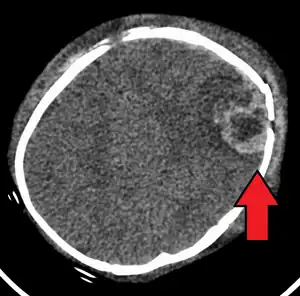

| An intraparenchymal bleed with overlying skull fracture from abusive head trauma | |

A skull fracture from abusive head trauma in an infant